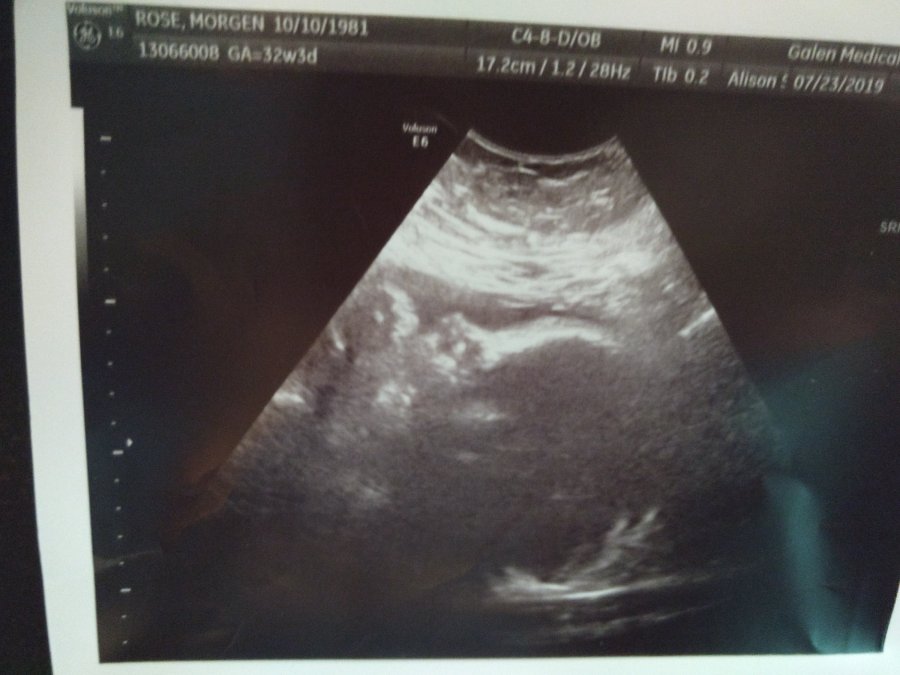

We are 32 weeks pregnant as of this week and went in for our ultrasound to follow up from 28 to see if Zora had gotten any bigger. I could tell you just from carrying around this new wiggly stomping person that she’d at least gotten busier. Our ultrasound, while she refused to cooperate and be photogenic, went well and she has jumped up to the 27th % for size and is now estimated at a little over 4lbs. The doctor said her other biophysical signs all looked good and that her fluid was in the “normal” range and it didn’t make her nervous. She said she expected to wait until around 39 weeks to plan our c section and has an optimistic outlook, while still wanting to keep a close watch on kiddo.